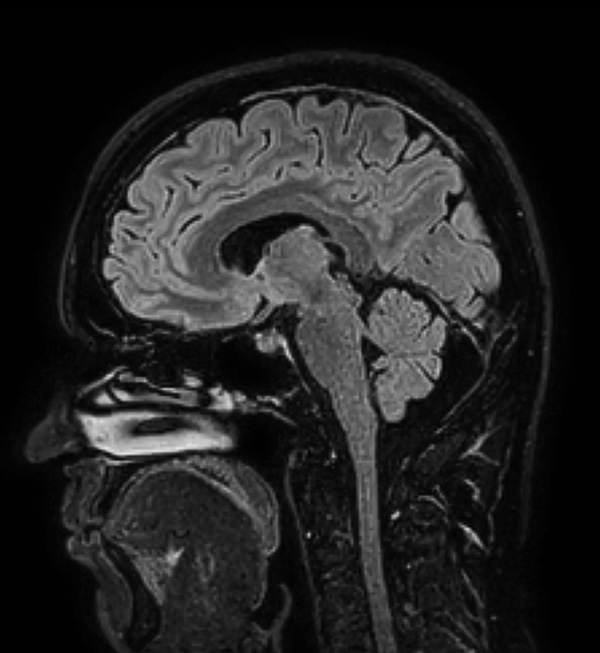

Comprehensive Brain imaging at 1.5T

Used Solution

• Clinical Application